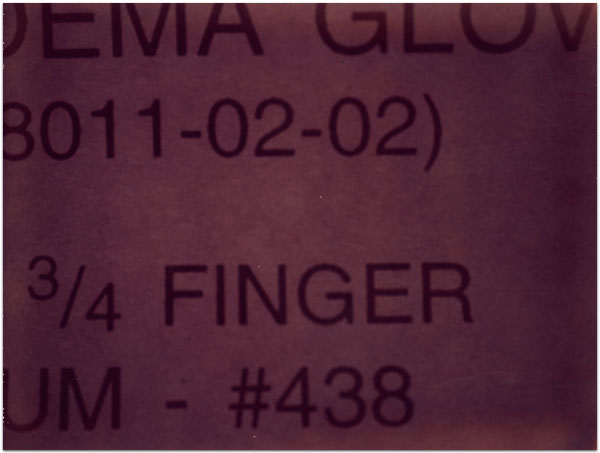

- Itis

- 2004

- 3.25″ × 4.25″

- Photographic montages of my hands & health paraphernalia on Polaroid Type 664 & 669 Film using a Daylab Printer.

- Frustrated by a lack of mobility and severe pain with my fingers, unable to accomplish any task requiring joint dexterity,

I noticed piles of health related papers strewn around. I layered these in a slide printer without removing

my hands, enlarging both onto the film.